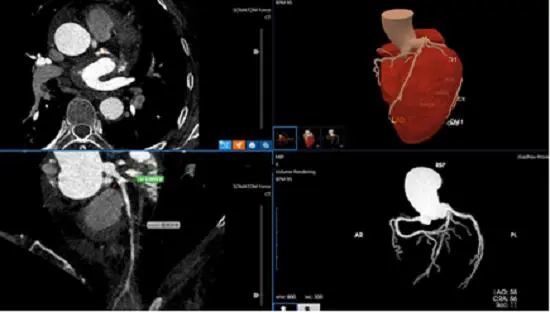

6月21日,筆者從貴州省人民醫(yī)院獲悉,該院醫(yī)學(xué)影像科診斷醫(yī)生近日運(yùn)用人工智能醫(yī)療技術(shù)僅用5分鐘,就為一名左前降支重度狹窄患者作出準(zhǔn)確診斷,經(jīng)人工智能輔助診斷冠心病技術(shù)快速準(zhǔn)確診斷為冠心病。確診后,在貴州省人民醫(yī)院心內(nèi)科施行冠狀動脈介入治療后,目前該患者術(shù)后恢復(fù)良好。